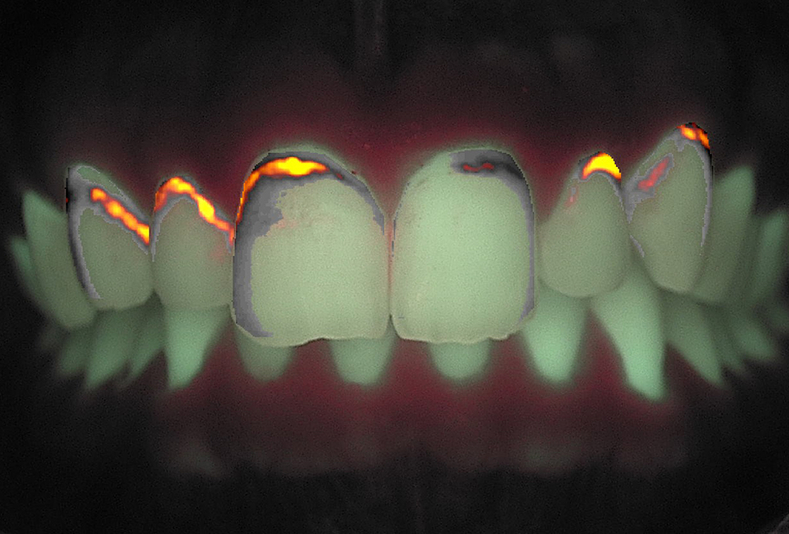

Casi clinici sull'applicazione della tecnologia QFL per il trattamento delle lesioni dello smalto

Igiene dentale

lesioni dello smalto

Applicazione della Fluorescenza quantitativa indotta per il trattamento delle lesioni dello smalto